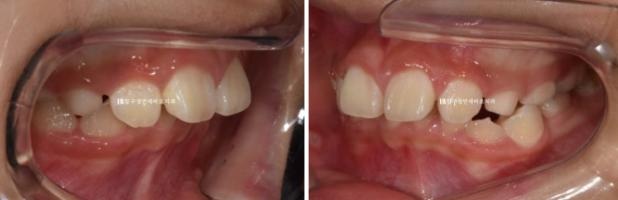

소아교정을 위해 찾아온 만 9세 어린이 입니다.

위 앞니가 아랫니를 가려서 안 보일 정도로 깊게 물리는 과개교합이고 윗니 돌출이 눈에 띕니다.

엑스레이를 보면 아직 유치가 8개나 남아있긴 합니다만 보증기간인 18개월 후면 영구치도 대부분 나올 것으로 예상이 됩니다.

악궁확장을 통해 영구치 맹출공간 확보, 윗니 돌출 해소, 앞니 배열을 목표로 장치 제작에 들어갔습니다